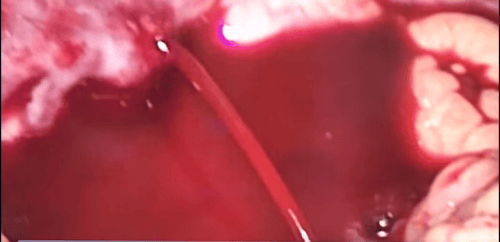

Chụp số hóa xóa nền và gây tắc búi giãn tĩnh mạch thực quản qua da là một thủ thuật can thiệp nội mạch. Dưới màn hình tăng sáng, vị trí giãn tĩnh mạch thực quản có thể đã vỡ hay chưa vỡ sẽ được tiếp cận và bơm vật liệu gây thuyên tắc nội mạch. Nhờ đó, dòng máu bị ngăn cách lưu thông, hiện tượng chảy máu sẽ được ngăn chạy hoặc giảm sức căng của búi giãn tĩnh mạch nên giảm được nguy cơ vỡ.

Sau đó, ống thông Cobra sẽ được thay bằng ống thông chụp mạch có đầu cong dạng đuôi lợn và có vị trí ở trong tĩnh mạch mạc treo tràng trên, ngay dưới vị trí hợp lưu với tĩnh mạch lách. Lúc này, bằng cách chụp số hóa xóa nền, hệ thống tĩnh mạch cửa ngoài và trong gan sẽ hiện lên khi bơm thuốc cản quang. Dưới màn hình huỳnh quang, bác sĩ sẽ đánh giá được hệ thống các nhánh bàng hệ và búi tĩnh mạch thực quản giãn đang vỡ gây chảy máu vào đường tiêu hóa trên.

Khi vị trí tổn thương đã được quan sát thấy, bác sĩ sẽ tiếp cận bằng cách dùng ống thông Cobra lựa chọn gốc của búi tĩnh mạch thực quản giãn. Một vi ống thông sẽ được đưa tiếp theo vào búi tĩnh mạch thực quản giãn qua ống thông Cobra để chụp mạch siêu chọn lọc qua vi ống thông nhằm xác nhận tình trạng búi tĩnh mạch giãn như thế nào và miệng vỡ gây chảy máu.

Tại đây, bác sĩ tiến hành can thiệp điều trị tắc búi tĩnh mạch thực quản giãn bằng vật liệu là vòng xoắn kim loại hoặc keo sinh học. Khi vật liệu được bơm vào vị trí tĩnh mạch giãn vỡ, dòng chảy sẽ được cầm lại và chấm dứt. Tuy nhiên, trước khi kết thúc, bác sĩ cần đánh giá sau can thiệp bằng cách thay ống thông Cobra bằng ống thông chụp mạch có đầu cong dạng đuôi lợn với đầu ống ở trong tĩnh mạch mạc treo tràng trên, ngay dưới vị trí hợp lưu tĩnh mạch lách.